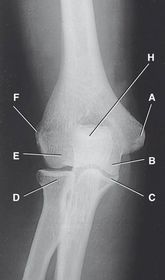

A. medial epicondyle B. trochlea C. coronoid tubercle D. radial head E. capitulum F. lateral epicondyle H. olecranon process